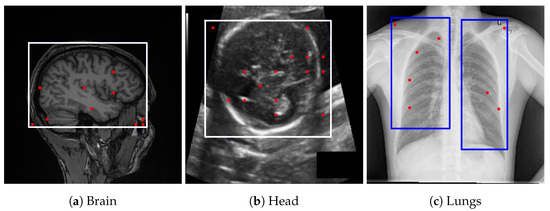

GPT-4o [13] demonstrated performance comparable to Gemini Pro 2.5 [9] in our internal evaluations; however, Gemini Pro 2.5, available from Google, was chosen for downstream experiments due to its consistent accuracy, stable API access, and available research funding for sustained API usage. It also outperformed LLaMA-based models, as shown in Figure 2. Model outputs were returned in JSON format and integrated directly into our segmentation pipeline. While the bounding box estimations generated by Gemini across multiple datasets were not sufficiently precise to serve as final segmentations, they consistently localized the region of interest. Despite occasional boundary inaccuracies, these estimations provided reliable spatial priors that effectively guided the SAM model towards more accurate segmentations, as illustrated in Figure 3.

Figure 3. Bounding box estimations by Gemini Pro 2.5 across different datasets. Blue rectangles and red dots indicate the prompts provided to SAM for generating segmentation candidates.